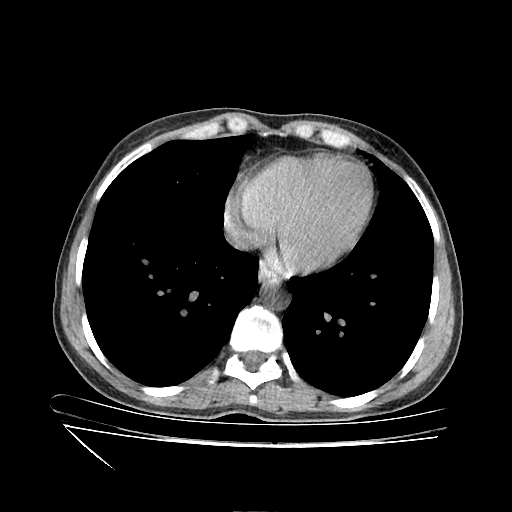

Original VENOUS CT scan

Full window (WL 1023.5, WW 4095 β†’ Low βˆ’1024, High +3071)

Actual HU range: [-160.0, 240.0]